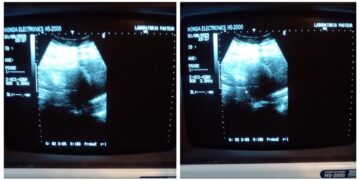

En entrevista para Imagen Noticias con Crystal Mendivil, la mujer aseguró que fue requerida en la clínica porque ya estaba en la semana 37 de su embarazo y sus bebés estaban a punto de nacer, pero al despertar le dijeron que se trataban de dos tumores.

Detalló que fue con la doctora Ivonne Castorena con quien se trató desde que le confirmaron a inicios de año que sí estaba embarazada luego de realizarse unos estudios, incluso afirmó que escuchó el corazón de sus mellizos durante las consultas.